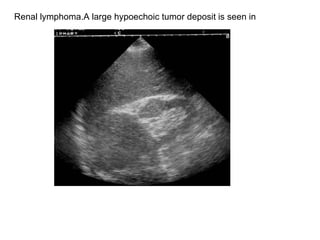

Renal lymphoma.A large hypoechoic tumor deposit is seen in

Infiltrated kidney(lymphoma).  The kidney is enlarged and the  internal architecture is destroyed.